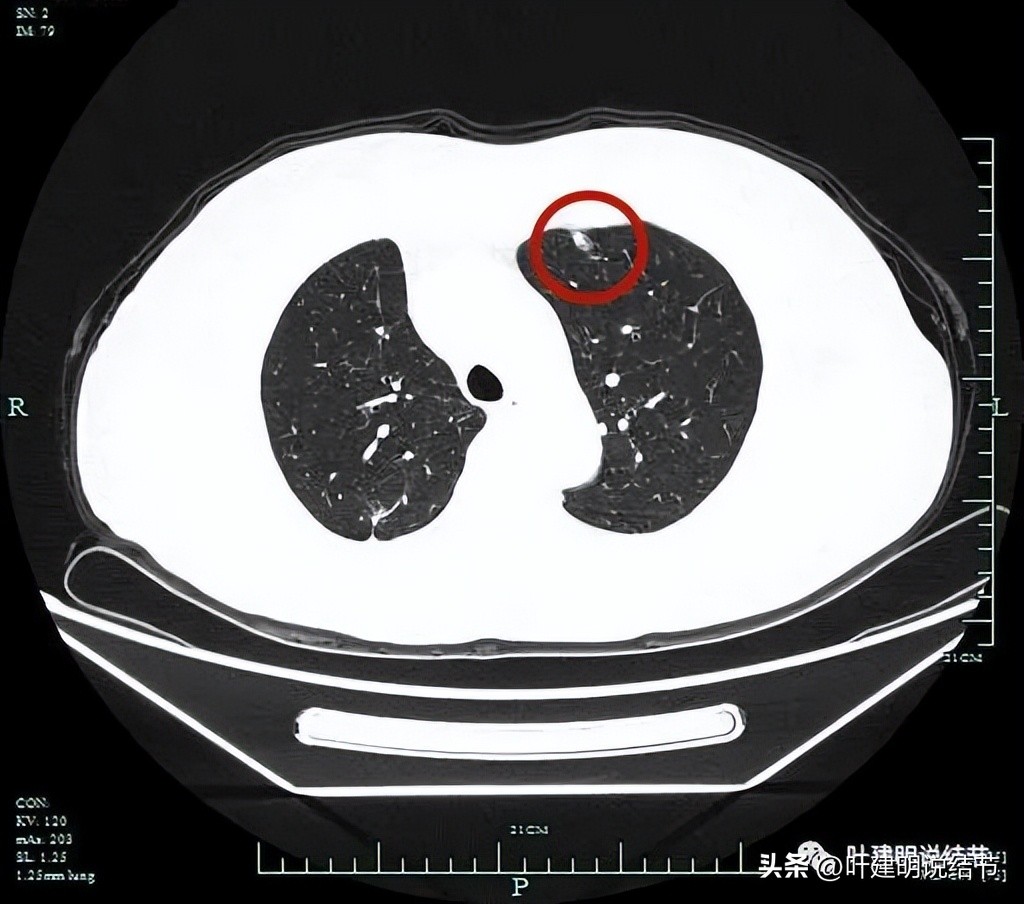

左上病灶1:磨玻璃密度,靠胸壁侧密度较高,有实性成分。

胸膜似略有影响,整体轮廓较清。

靶扫描显示主病灶混合磨玻璃密度,边缘实性成分(粉色箭头);瘤肺边界清(红色箭头);部分边缘似有毛刺(紫色箭头)。

灶内实性成分(粉色箭头)以及微血管进入(桔色箭头);整体密度不均,轮廓与瘤肺边界清(红色箭头)。

微血管征、毛刺征、混合磨玻璃密度、胸膜间隙征(黄色箭头)。

血管进入,混合密度,轮廓清。